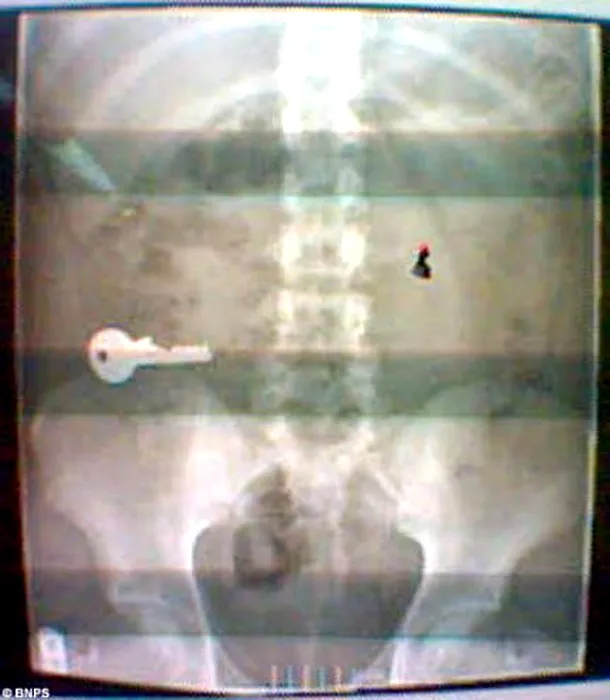

Cele mai ciudate lucruri pe care doctorii le-au găsit în stomacul pacienților. GALERIE FOTO